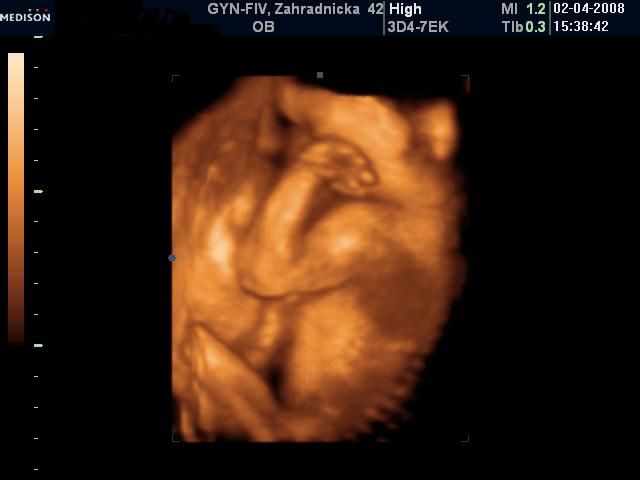

Bol to krásny deň napriek upršanému počasiu (aspoň sme sa nepotili) ;-) Všetci ma utešovali, že to nám prší šťastie a ja tomu verím.